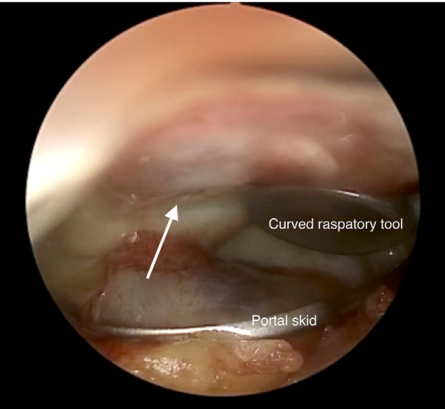

Vùng tổn thương mục tiêu được làm khô bằng gạc. Dụng cụ nạo cong được sử dụng để ước lượng kích thước vùng tổn thương. Màng collagen đã ngâm BMAC sau đó được cắt theo hình dạng và kích thước phù hợp với vùng tổn thương, sử dụng kéo Metzenbaum.

Đáy vùng tổn thương được phủ một lớp mỏng keo sinh học Tisseel (Baxter, Deerfield, IL) và để khô trong khoảng 1 phút. Sau đó, hỗn hợp sụn băm nhỏ trộn với BMAC được đưa vào phía trên lớp Tisseel đã khô bằng trocar bơm chuyên dụng. Lớp sụn băm nhỏ này tiếp tục được cố định bằng một lớp Tisseel thứ hai (Hình 5). Tiếp theo, miếng Chondro-Gide đã được cắt đúng kích thước vùng tổn thương sẽ được đưa vào vị trí bằng một kẹp động mạch nhỏ, kẹp nhẹ phần chóp của mảnh ghép để tránh làm tổn thương cấu trúc scaffold (Hình 6). Một lớp keo Tisseel nữa được thêm lên để cố định scaffold tại chỗ. Dụng cụ nạo cong hoặc đầu nạo McDonald được dùng để ấn nhẹ và làm phẳng scaffold áp sát vào nền tổn thương (Hình 7). Lớp keo Tisseel cuối cùng được phủ lên và để khô ít nhất 5 phút.